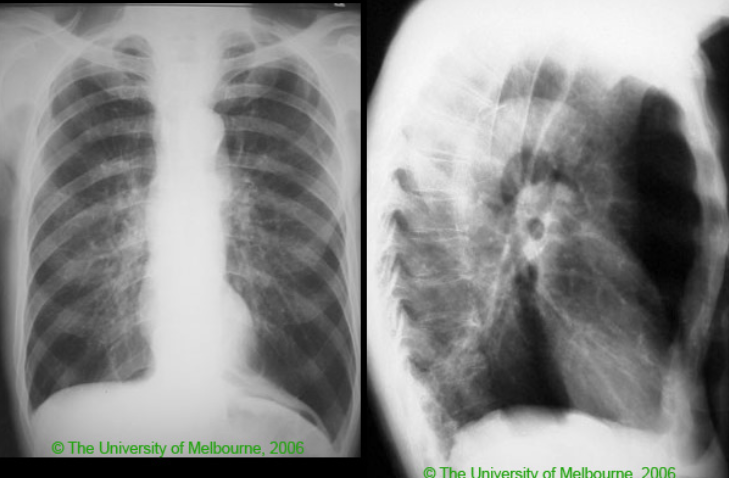

75yo male with CHF presents with dyspnoea. Crackles are heard at the lung bases on examination

Pulmonary oedema